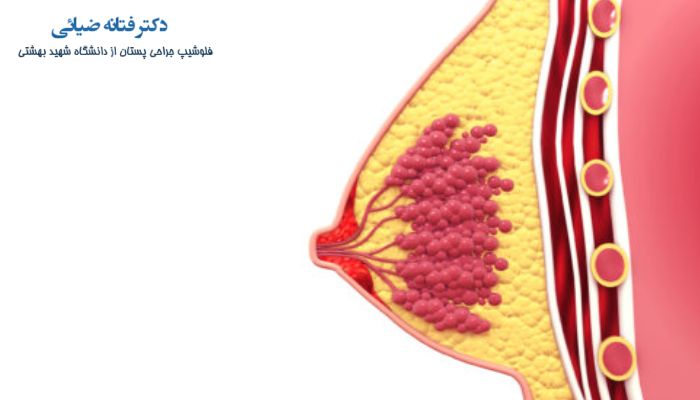

◀ سرطان

ترشح نوک پستان میتواند به دلیل سرطان پستان باشد، البته این مورد غیر رایج است اما 5 درصد خانم هایی که به سرطان سینه مبتلا می شوند دارای ترشح از نوک سینه هستند. نوعی از سرطان پستان که (paget) نام دارد معمولا با زخم و فرسایش نوک سینه همراه است و ترشحات خونی از آن به وجود می آید.